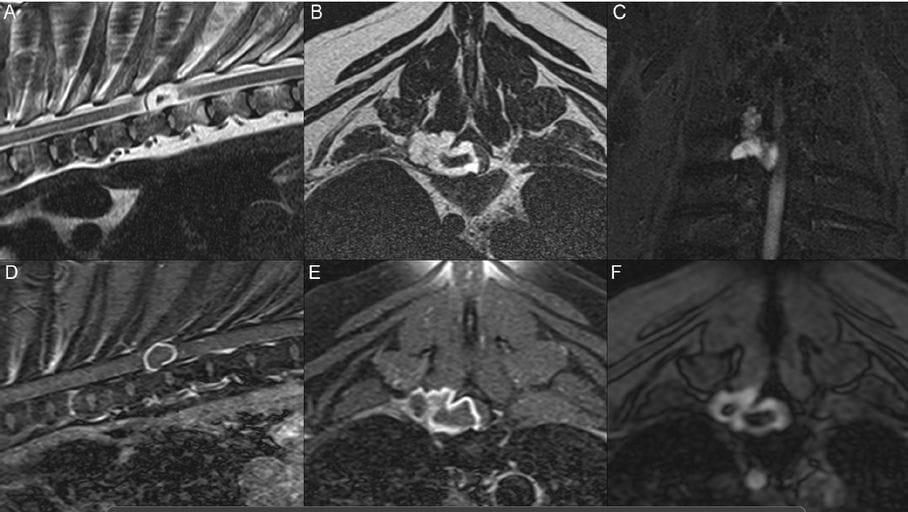

Magnetic resonance imaging sequences of the thoracic region in a 7-year-old spayed female Weimaraner mix with pelvic paraparesis and proprioceptive ataxia. In sagittal views, the head is to the left of the image. In transverse views, the right side of the patient is on the left side of the image. Sagittal (A) and transverse (B) T2 images; dorsal STIR (C), sagittal (D), and transverse (E) postcontrast T1-weighted images with fat saturation; and transverse gradient echo (F) images. A T2-hyperintense, STIR-hyperintense, rim contrast-enhancing mass is present at T6, extending laterally in a dorsocranial direction from the spinal canal toward the right hypaxial muscles. In the transverse gradient echo image (F), the lesion displays susceptibility artifact and was associated with hemorrhage and decreased cartilaginous matrix on histopathology. In the dorsal STIR image (C), the mass is severely compressing the right aspect of the spinal cord and disrupting the hypointense signal of the T5 right rib. Mild atrophy and contrast enhancement is present within the right hypaxial muscles.

MRI revealed a large extradural, T2-hyperintense, contrast-enhancing mass at the T6 vertebra causing spinal cord compression. The lesion extended into the right epaxial muscles and was suspected to be neoplastic. CSF analysis showed mild albuminocytologic dissociation. Necropsy and histopathology confirmed a multinodular, infiltrative chondrosarcoma, causing bone destruction, gliosis, and myodegeneration. Radiographs failed to detect the lesion, but MRI clearly delineated its characteristics.